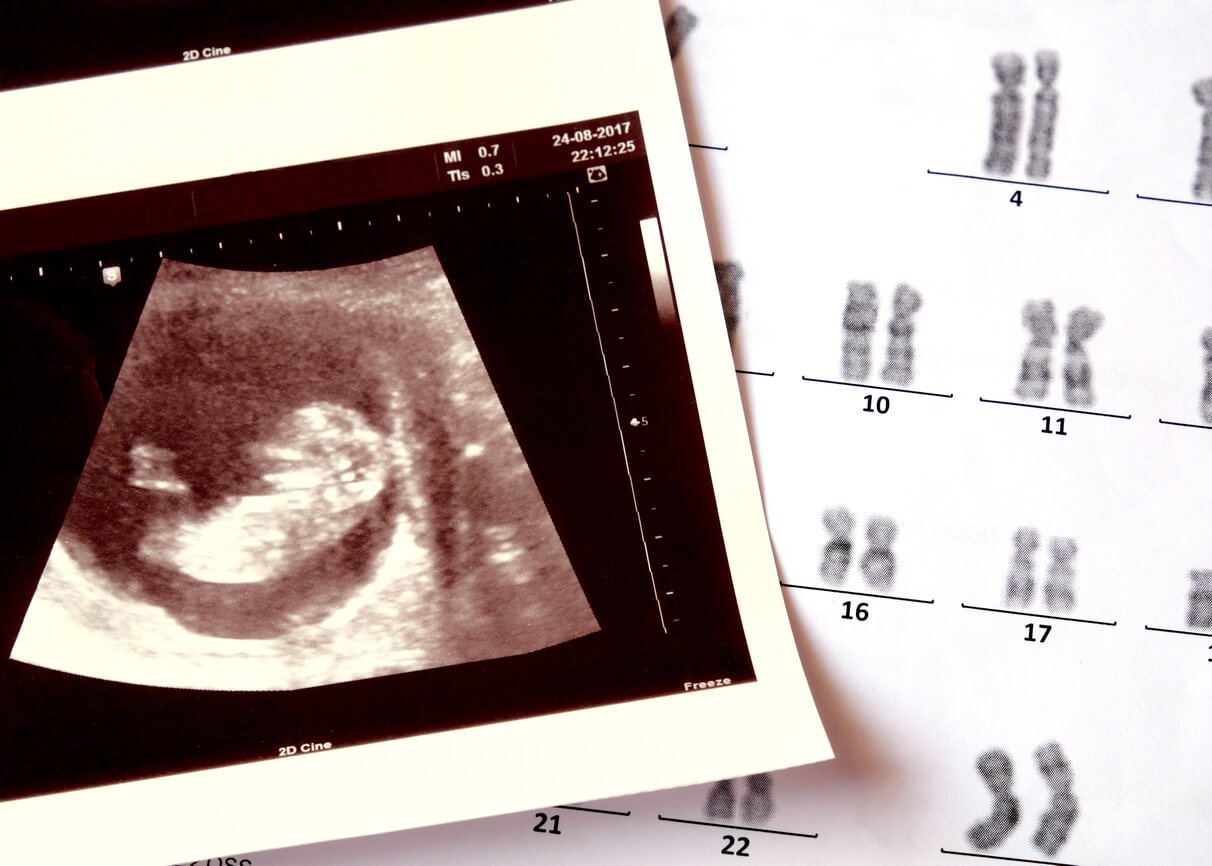

Ces 3 résultats sont ensuite comparés à d’autres données (âge maternel, poids et origine ethnique) sur un ordinateur. A partir de là, on obtient le pourcentage de risque que le bébé souffre effectivement d’une des trisomies les plus fréquentes, dans les chromosomes 13, 18 ou 21.

Au contraire, lorsqu’il est inférieur à 1/270, la probabilité que le bébé soit effectivement porteur d’un défaut dans ses gènes est élevée. Pour corroborer ce résultat, le spécialiste indiquera la réalisation d’autres tests diagnostiques. Tels que l’amniocentèse ou la biopsie des villosités choriales. Les deux tests prénataux sont invasifs, mais donnent des résultats très fiables.